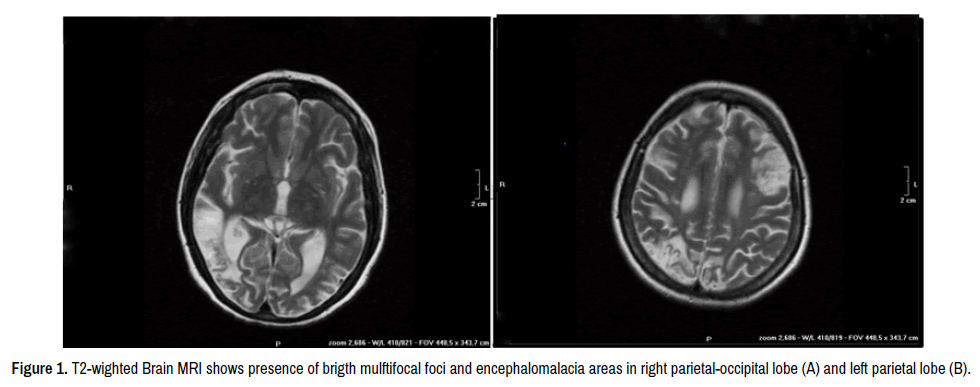

Brain magnetic resonance (MRI) is an helpful imaging method to detect brain injury. Bright small and multifocal foci on T2-weighted MRI are often localized in periventricular deep white matter or in pons, but other sites could be involved and cortical atrophy may be observed. Cerebral angiography may reveals an obliterating non-inflammatory arteriopathy with stenosis of intracranial vessels, artero-venous malformations and presence of fine collateral vessels [10,11]. Current treatment is based on oral anticoagulation in association, in autoimmune-related SS, with immunosuppressant drugs, such as corticosteroids, cyclophosphamide, azathioprine, with few results. Intravenous Immunoglobilins (IVIG) have been also used to treat the vasculopaty, while the use of prostaglandins analogues has been reported for the treatment of skin ulcers [10-13]. To our knowledge, the use of anti-CD20 (Rituximab-RTX) in autoimmune-related SS has not been reported so far. We report here for the first time, the case of a 40 years old woman with a SLE-related SS with anti-phospholipid antibodies, treated with RTX with a good response after two years of follow-up.

Brain MRI showed bright small and multifocal foci on T2-weighted sequences and encephalomalacia, revealing a severe brain involvement (Figure 1), although she was on oral anticoagulation and on azathioprine. Pulmonary angio-CT scan and lung scintigraphy excluded a chronic thromboembolism. High resolution CT of the chest showed the presence of nonspecific interstitial lung disease. Head and neck ultrasound and oftalmologic evaluation resulted normal. According to these findings a diagnosis of “SLE-related Sneddon’s Syndrome with presence of anti-phospholipid antibodies and with Interstitial Lung disease" was performed. We increased oral anticoagulation treatment, maintaining INR between 3-4, and introduced ASA and Metilprednisolone at a dose of 4 mg/die. Considering the progression of the disease, the lung involvement and the presence of high levels of autoantibodies, we decided to treat the patient with RTX and two cycles were carried out six months apart. After two years of follow up, no ischemic events have been documented. Patient is continuing oral anticoagulation and neuro-cognitive rehabilitation, with a good clinical response.

Figure 1. T2-wighted Brain MRI shows presence of brigth mulftifocal foci and encephalomalacia areas in right parietal-occipital lobe (A) and left parietal lobe (B).